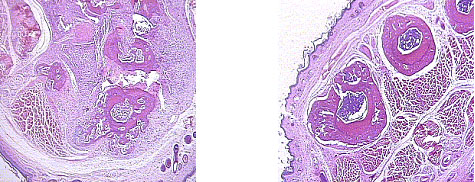

(2) Effects of dendritic cells onto progression

We wondered if GH could modulate or help inflammatory

processes in systemic or local inflammation. Its role

in inflammation is not clear, but it could act an immune

enhancer. Also, in a clinical point of view, GH was regarded

as an immune suppressor. In preliminary experiment within

our Lab., GH suppressed interleulin(IL)-1 beta, which

was one of preinflammatory cytokines. We want to investigate

GH role within autoimmune processes. We made autoimmune

inflammation with type II collagen, which would develop

arthritis in mice. We called it collagen- induced arthritis

(CIA) in mice. It had been regarded as an animal model

of rheumatoid arthritis. We would check specific changes

of some inflammatory cytokines with CIA animals. It might

be helpful for knowing GH roles in autoimmune reactions.

|

Figure 2. Arthritis control(left): this

slide shows multiple periosteal reaction, cartilage metaplasia,

and bony erosions. Heavy inflammatory cells, Lymphocytes

and histiocyte infiltrates around the destructed tissue.

DC treated (right): Some periosteal reactions are shown.

Inflammatory cells are not found, and lining synoviums

are normal looking. |